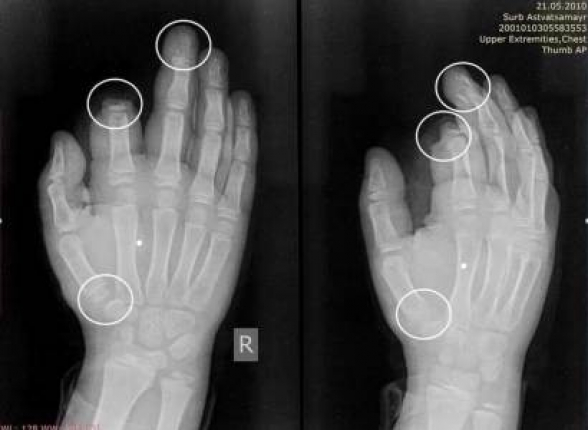

«Ամանորի գիշերը «Սուրբ Աստվածամայր» ԲԿ են դիմել պայթուցիկներից ու հրավառություններից տուժած 6 անձ։ Նրանցից 4-ը ստացել են ամբուլատոր բուժօգնություն, իսկ 2-ը շարունակում են մնալ բժիշկների հսկողության տակ։ 10-ամյա տղայի մոտ ամպուտացված է եղել մեկ մատը (պոկված մատը վերականգնման ենթական չի եղել), իսկ մյուս մատները հաջողվել է փրկել։ Իսկ 16-ամյա տղան պայթուցիկի հետևանքով մատների կոտրվածքներ է ստացել, վնասվել են նաև ձեռքի մկանները»,-գրել է նա: